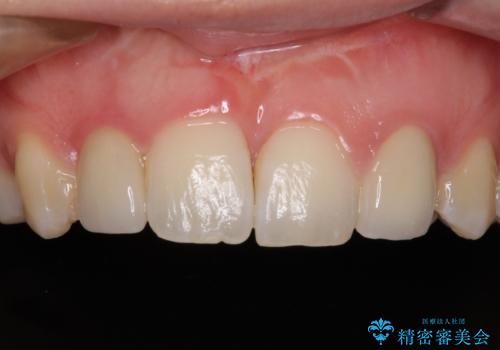

- 他院で矯正治療を終え、上顎前から2番目の歯の大きさを気にして来院された患者様です。

右側は小さく、左側は欠損により犬歯が前から2番に来ている状態でした。

矯正治療の段階で、矮小歯は前後にスペースが作ってあったため、極力左右対称の歯冠形態となるように補綴治療を行うこととしました。

歯根の太さや幅が左右で異なるため、歯肉ラインはどうしても左右非対称となってしまいますが、とても自然な口元となりました。